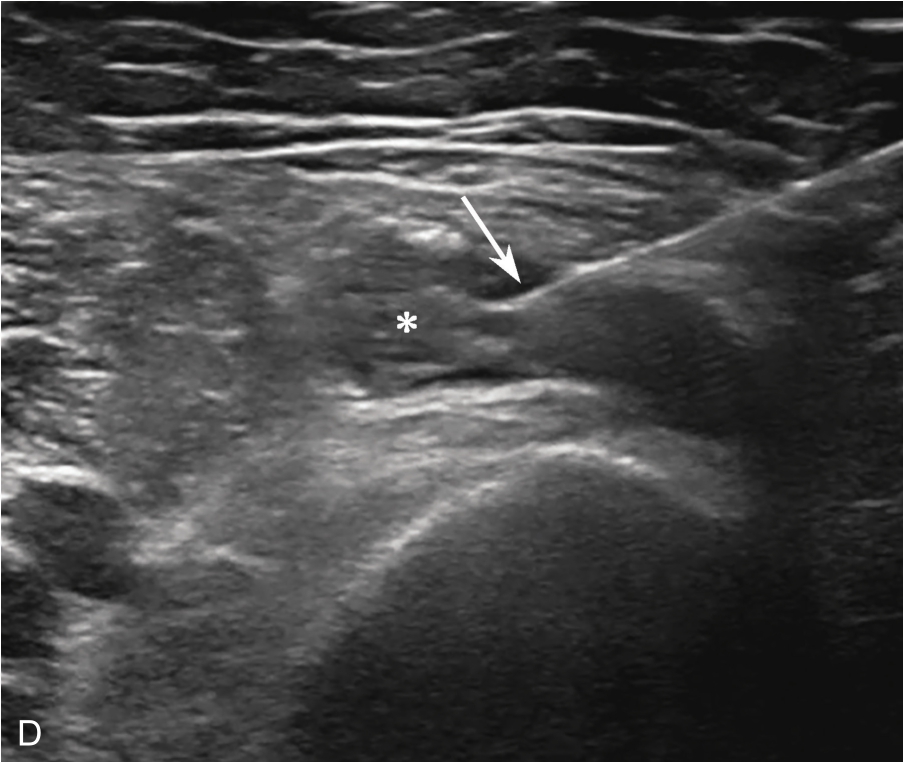

2.当针尖进入滑囊后(图2-1-5),可推注少量药物,若推注顺利可观察到滑囊扩张及药物的弥散(图2-1-6),同时也表明针尖准确位于滑囊内,可继续推注混合药物3~5ml。若推注受阻,原因有可能是针尖在滑囊组织内,需重新调整针尖,也可能是滑囊内粘连明显所致,可加大力度,利用液体推注的压力松解粘连,松解后可见粘连带呈线状稍强回声(图2-1-7),也可在粘连远端重新选择部位注入药物,这类患者可能需要多次治疗才能达到较好的疗效。

▲ 图2-1-5 超声引导下肩峰下-三角肌下滑囊穿刺治疗超声图

箭头:显示穿刺针尖进入滑囊;星号:冈上肌腱;H:肱骨头